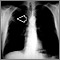

Pulmonary nodule - front view chest x-ray

Lung nodule - front view chest x-ray